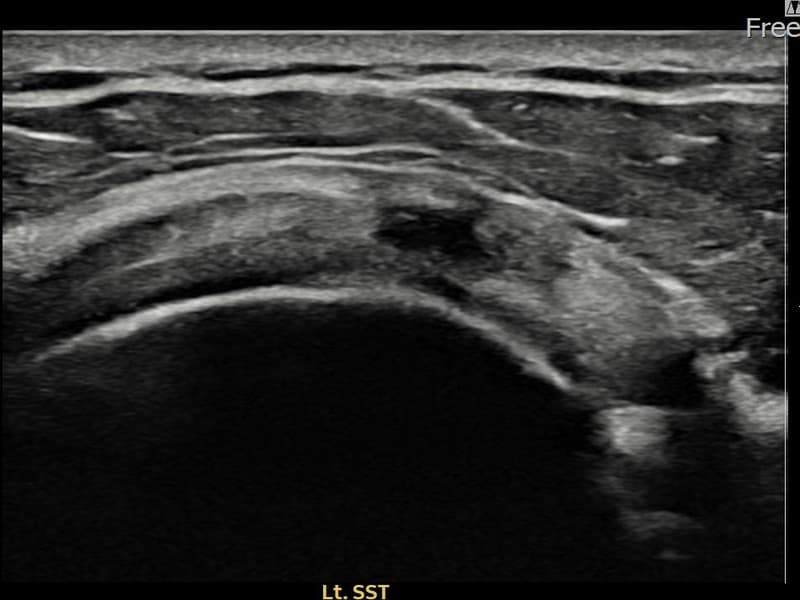

超音波検査にて左 棘上筋腱 関節面側部分断裂(8mm × 3mm (腱厚の約33%欠損))を確認。縫縮術施行後、腱の連続性が回復し、日常生活に復帰されました。

施術前

術前超音波にて左 棘上筋腱 関節面側部分断裂・左肩棘上筋腱のエコー不連続と腱欠損(8mm × 3mm (腱厚の約33%欠損))を確認。術後超音波では断裂部位が再生組織で充填され、腱の連続性回復とエコーパターンの正常化が確認されました。